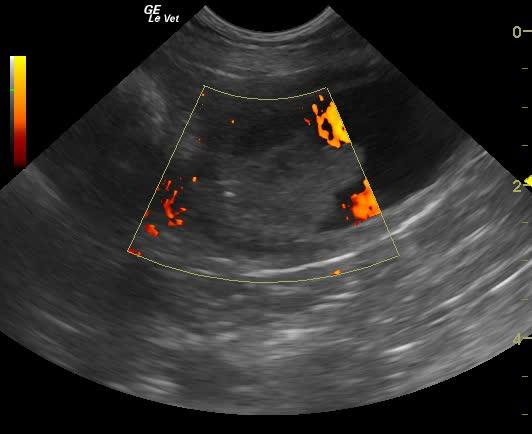

A 10-year-old neutered male West Highland Terrier was presented for hematuria. The only finding on physical examination was a soft cardiac murmur. Abnormalities on urinalysis were 1+ bilirubin and trace blood.